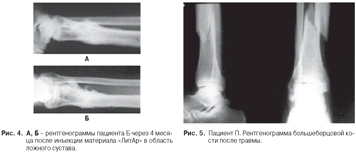

Для сравнения приведены примеры замещения

опухолей мыщелков бедренной кости хроносом и пористым углеродом.

Сравнение замещения дефектов губчатой кости

хроносом и пористым углеродом показало, что после имплантации хроноса через год

рентгенологически определяются фрагменты имплантированного материала, т. е. его

перестройка к этому времени не заканчивается. При использовании пористого

углерода определить материал на рентгенограммах крайне сложно. Положительным

качеством пористого углерода является возможность врастания в него сосудов и

костной ткани, следовательно, - восстановления питания субхондраль-ной зоны

кости и самого хряща.